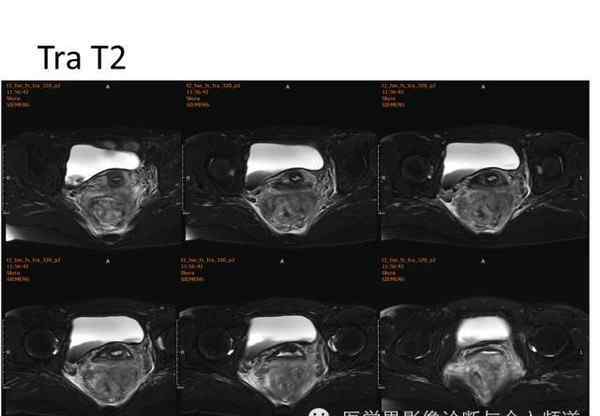

核磁共振平片扫描和增强扫描显示:

盆腔内可见弥漫性长T1长T2异常信号,FS-T2WI可见高信号,涉及直肠左前壁、直肠侧韧带和宫颈等。边界不清,盆腔可见条带状FS-T2WI高信号强度。注射钆喷酸葡胺后,病情明显加重。